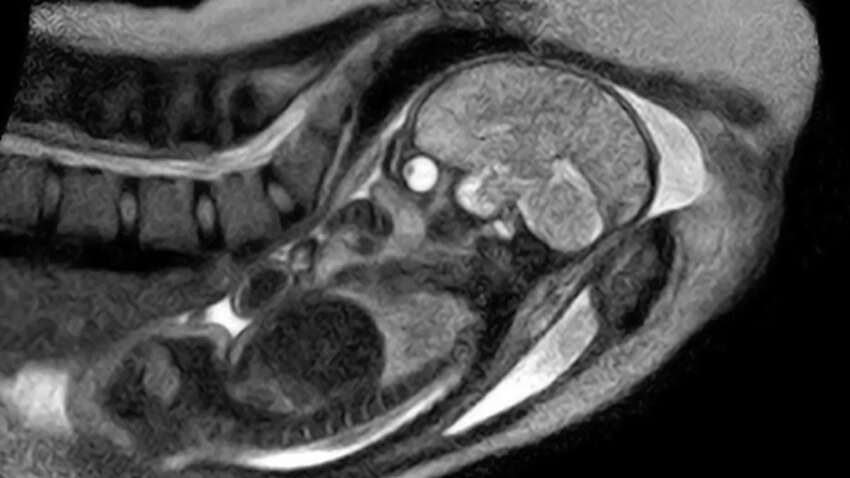

Останні 45 хвилин пологів зафіксували серією знімків МРТ, які згодом змонтували у 25-секундне прискорене відео. На ньому видно фінальні перейми, рухи внутрішніх органів матері та появу голівки дитини. Запис дозволив медикам вперше з високою точністю побачити положення плода і його шлях через родові шляхи.